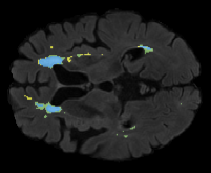

We evaluated our method in segmenting WMH from T1-w images using: a) Synthesized FLAIR images by treating the synthesis as a preprocessing step – we will refer to this method as offline synthesis; b) Synthesized FLAIR images using the proposed method, and c) without any synthesis – we will refer to this method as Unimodal. Baseline methods are illustrated in Figure 2

Table 2: Segmentation results for all proposed methods, each column represent a different slide in the image, blue areas are regions which were correctly labeled, false positives are shown in green, and false negatives in yellow

In order to better understand the above results, we visually analyzed the output segmentation performed for each method. Table 2 shows the results for three different slices (one slice per column). As illustrated, the proposed method is able to produce less false positives. It is also important to note that, unimodal segmentation is the one that produces more false positives, showing the advantage of using synthetic data. Regarding the nature of false positives, it can be easy to see in the third column a large number of false positives are on the border of periventricular lesions for the Unimodal method in comparison to the proposed method. Also from the first and second column, it can be observed that Unimodal tend to produce more small regions of false positives near to cortical areas. Removing such false positives requires additional post-processing steps, therefore, it is of value avoid this kind of over-segmentation. It can also be noted that synthesis methods tend to produce the same kind of false negatives, this may be due to the blurring effects in synthesized images since the information available during testing is limited – which otherwise is available from a FLAIR sequence.